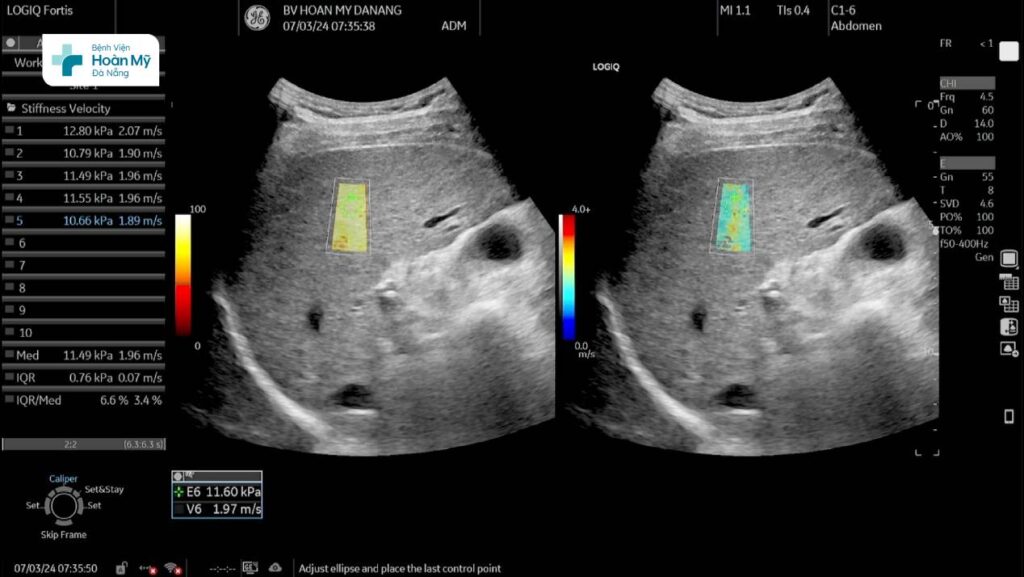

Hình ảnh siêu âm chẩn đoán mức độ xơ hóa gan trên máy siêu âm cao cấp LOGIQ Fortis thế hệ mới tại BV Hoàn Mỹ Đà Nẵng

Một ví dụ khi ứng dụng siêu âm đàn hồi mô trong chẩn đoán xơ gan như sau: Một người bệnh nam, gần đây thấy mệt mỏi nên đến khám tại Bệnh viện Hoàn Mỹ Đà Nẵng, được bác sĩ cho siêu âm bụng, trên siêu âm thường quy thấy cấu trúc gan thô, khi thực hiện siêu âm đàn hồi mô gan đo được độ cứng 11,49 kPa (IQR/Med # 6,6%) tương ứng xơ hóa gan độ 3.